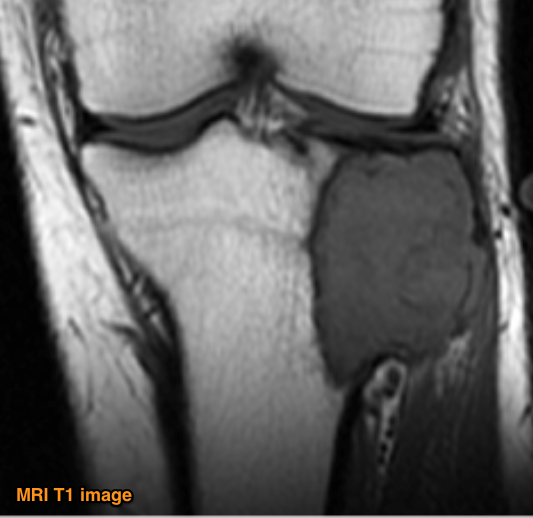

MRI